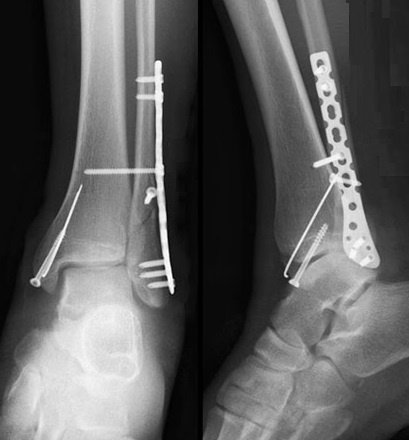

Хворій рекомендовано оперативне втручання, на яке хвора дала згоду. При госпіталізації проведено необхідні інструментальні та лабораторні методи обстежень та огляд консультантами (терапевтом та анестезіологом). В екстреному порядку хворій проведено оперативне втручання – Відкрита репозиція з МОС перелому зовнішньої кісточки стягуючим гвинтом та нейтралізуючою пластиною LCP та відкрита репозиція з МОС внутрішньої кісточки спицею та гвинтом. Після оперативного втручання хвора переведена в палату. З 2-3 доби хворій дозволено активні рухи у г\ступневому суглобі без навантаження на ліву н\кінцівку. Шви знято на 11 добу, хвора в задовільному стані з наданими рекомендаціями щодо тактики подальшого лікування виписана з травматологічного відділення.

Хворому рекомендовано оперативне втручання, на яке була отримана згода. При госпіталізації проведено необхідні інструментальні та лабораторні методи обстежень та огляд консультантами (терапевтом та анестезіологом). В екстреному порядку хворому проведено оперативне втручання – Відкрита репозиція з МОС перелому зовнішньої кісточки дистальною м\гомілковою пластиною LCP та відкрита репозиція з МОС внутрішньої кісточки гвинтами та антиковзною пластиною. Після оперативного втручання хворий переведений в палату. З 2-3 доби хворому дозволено активні рухи у г\ступневому суглобі без навантаження на праву н\кінцівку. Шви знято на 11 добу, хворий в задовільному стані з наданими рекомендаціями щодо тактики подальшого лікування виписана з травматологічного відділення на амбулаторне лікування